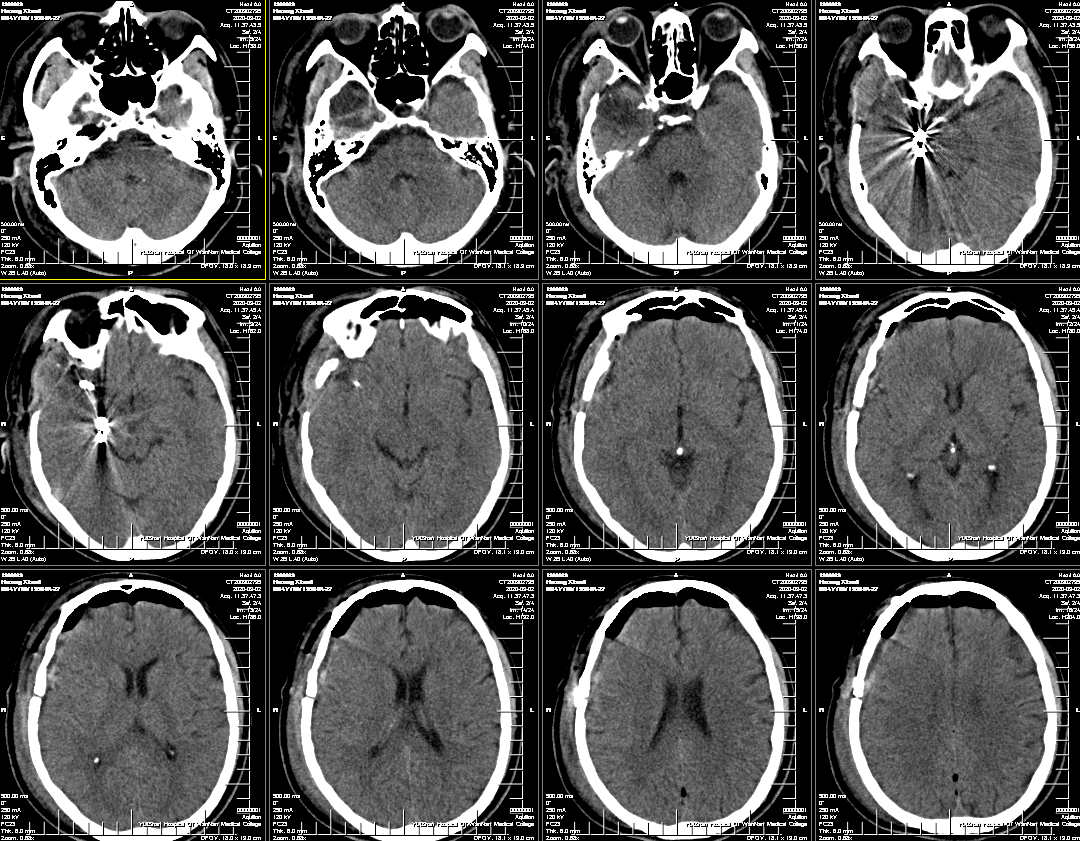

外院头颅CT示右侧颞叶钙化灶,头颅MRI示见右侧颞叶流空信号,考虑动静脉畸形。

入院后脑血管造影检查提示:右侧颞叶动静脉畸形,由右侧大脑中动脉两分支血管参与供血,右侧大脑后动脉一分支血管参与供血,畸形团大小约1.1*1.3cm,通过侧裂静脉经皮层静脉引流入上矢状窦前部;并可见右侧大脑后动脉供血畸形团的分支血管血流相关性动脉瘤两枚。

1. 通过椎动脉先将Echelon 10微导管在导丝导引下超选至远端动脉瘤,填塞弹簧圈(Cosmos 4mm/12cm,Jasper 3.5mm/10cm,Axium 3mm/8cm,Jasper 2.5mm/8cm),然后逐渐回撤微导管至近端动脉瘤填塞(Axium Prime 4mm/12cm),最后可见向畸形团供血明显减弱,远端动脉瘤不显影,近端动脉瘤仍有显影。

将Echelon 10微导管超选至右侧大脑中动脉分叉部分支血管远端,微导管造影确认系畸形团供血动脉,DMSO冲管后注射Onyx胶再行造影,可见该分支血管远端闭塞,予以撤出Echelon 10微导管。

用Apollo微导管超选大脑中动脉M1段分支血管直至畸形团内,进行微导管造影确认微导管进入畸形团,DMSO冲管,缓慢注射Onyx 18,路图下可见胶在畸形团内弥散,最后颈内动脉造影可见畸形团完全不显影,但是胶反流导致拔管困难,透视下可见血管移位变形明显。

考虑到患者术前癫痫,且介入术中患者拔管困难,予以行开颅手术切除畸形血管团,并拔出微导管。术中可见微导管及注射的Onyx胶(血管内黄色部分及黑色部分),游离血管后近端用临时阻断夹阻断,远端剪断,打开临时阻断夹将微导管自股动脉鞘拔出,然后切除畸形团。术后复查头颅CT提示钙化及介入术中胶均已切除。